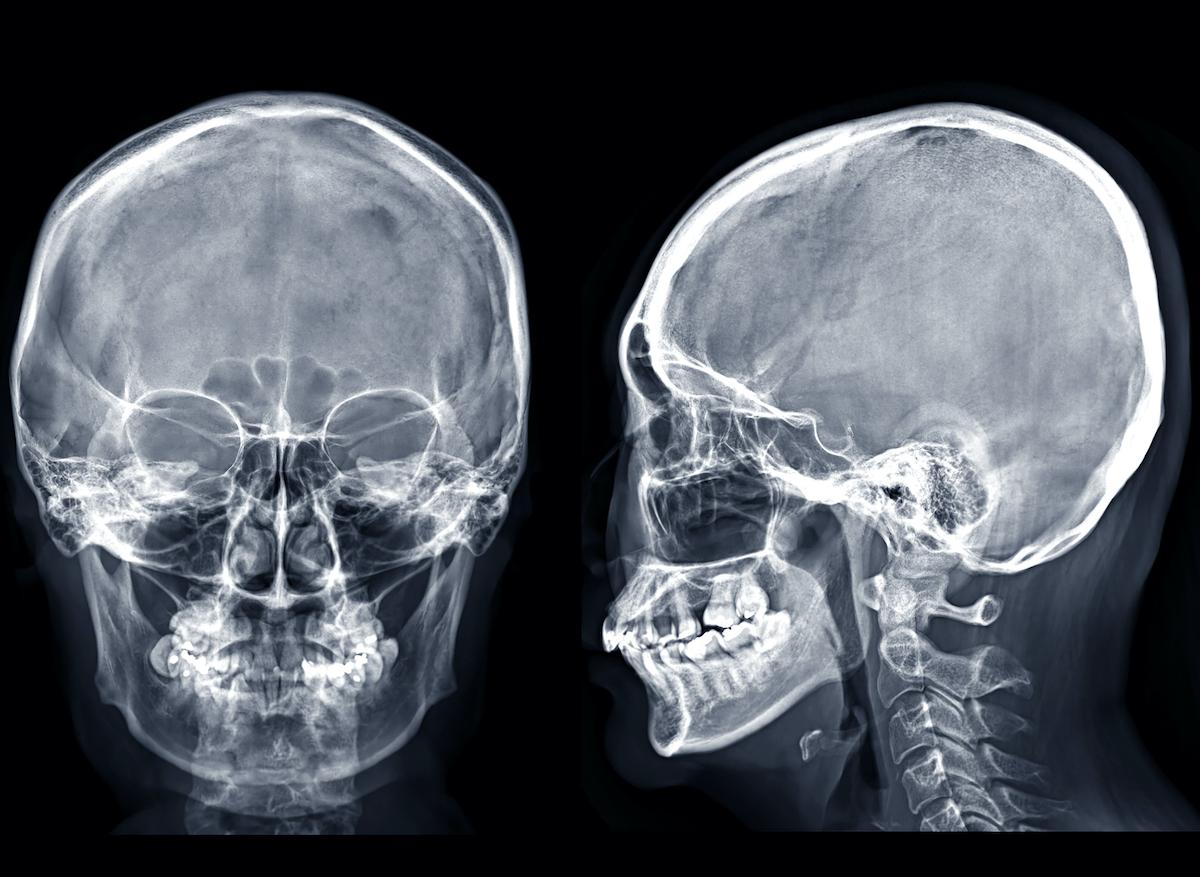

Les chercheurs ont réalisé un PSMA PET-scan, un type d’imagerie médicale utilisé pour détecter et suivre des cancers de la prostate en ciblant un marqueur spécifique, le Ga-PSMA. Les chercheurs ont également injecté un traceur radioactif. La combinaison de ces deux procédés a conduit les chercheurs à observer une nouvelle structure à l’arrière du nasopharynx. “Les sujets ont trois ensembles de grosses glandes salivaires... mais pas là normalement, s’est étonné Wouter Vogel, oncologue à l’institut néerlandais du cancer. Pour autant que nous le sachions, les seules glandes salivaires ou muqueuses du nasopharynx sont microscopiquement petites, et jusqu'à 1 000 d'entre elles sont réparties uniformément sur la muqueuse. Imaginez donc notre surprise lorsque nous avons découvert ces glandes !”Les trois types de salivaires jusqu’alors connus se situent soit près des oreilles, soit en dessous de la mâchoire sois sous la langue. Les deux nouvelles glandes découvertes au centre du crâne ont été surnommés “glandes tubaires” par les chercheurs. Cela fait référence à leur position anatomique, juste au-dessus d'une structure appelée “torus tubarius”.

Les glandes tubaires ont été observés sur le scanner des 100 patients inclus dans l’étude. Elles l’ont également été chez deux patients décédés et les autopsies ont révélé que ces glandes sont reliées à de grands conduits de drainage. Cela indique que les glandes ont bien une utilité et sont reliés à une autre partie du corps. Les chercheurs suggèrent que leur rôle pourrait être de lubrifier le nasopharynx et l'oropharynx, les deux parties supérieures du pharynx, pour faciliter le mécanisme de déglutition.Des recherches supplémentaires sont nécessaires pour mieux comprendre le rôle de ces glandes. Cette découverte pourrait avoir des conséquences sur les traitements des cancers puisque les les glandes salivaires sont très sensibles et peuvent être abîmées durant les thérapies et doivent être évitées. Les traitements par radiothérapie des cancers de la tête et du cou pourraient entraîner une irradiation des glandes tubariennes qui conduiraient à des complications chez les patients. Cela pourrait expliquer pourquoi les personnes souffrant de ce cancer souffrent souvent de sécheresse buccale chronique et de problèmes de déglutition.